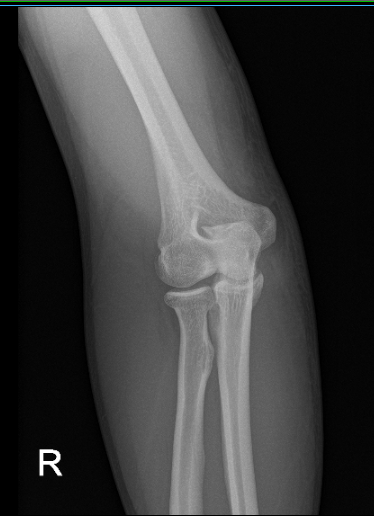

He is here for his one week postoperative visit with X-rays right elbow. He Denies fever, chills and is able to return to work after a week of operation. X-ray showed that previous surgery is healing and soft tissue swelling overlying the olecranon process.

Postoperative X-ray of right elbow